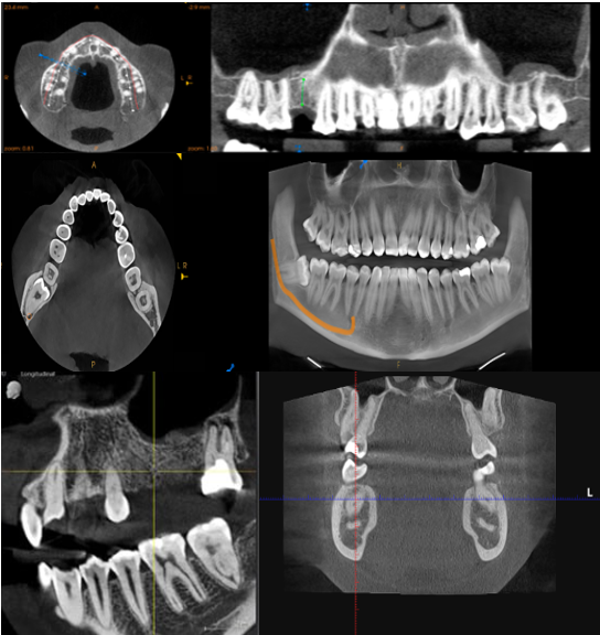

Medium F.O.V CBCT

Maxilla or Mandible.